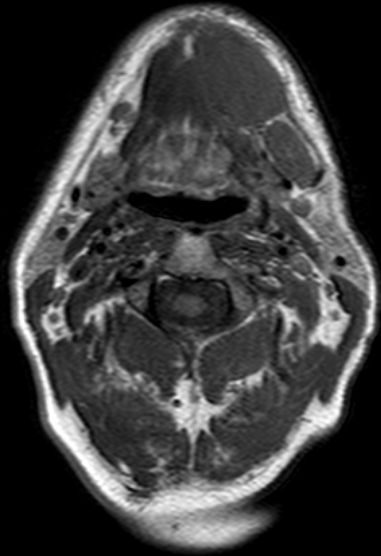

| MRT | 54-jähriger Mann mit Mundbodenkarzinom links cT4 cN2 M0. Zunächst Schmerzen im linken Unterkiefer, dann spontan Zahnausfall. Zahnarzt: kein Tumorverdacht. Dann Schwellung am vorderen Unterkiefer links. Klinisch 8 cm große, derbe, fixierte Schwellung am linken Unterkiefer, die bis zur Kinnspitze reicht und etwas auf die Gegenseite herüberreicht. Enoral Fäden nach Extraktion sichtbar. Kein Tumorulcus! Der Unterkieferknochen ist medial kranial arodiert und wird über weite Strecken vom Tumor eingeschlossen. Der Tumor durchbricht die Mundbodenebene nach kaudal und reicht bis zum Zungenbein. | ||